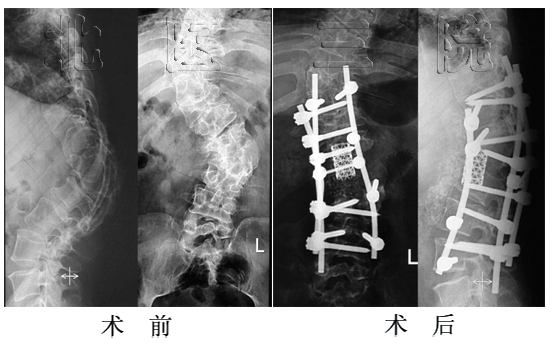

女性,65岁,成人腰椎侧凸,侧凸角度46o,行侧凸矫形固定、植骨融合,术后侧凸角度减小为5o